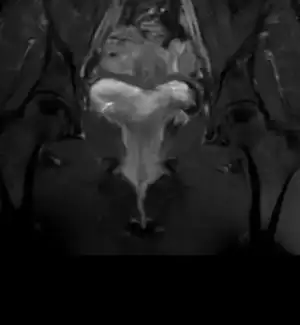

Mr dan rahmimin goruntusu arkuad uterus

Eklentiler

• IMG_20230617_211742_809.webp

IMG_20230617_211742_809.webp

4,2 KB · Görüntüleme: 119